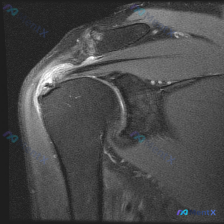

整理了一份肩部MRI病例讨论材料,医生的核心问题是排查盂唇病变,但看影像发现了一些矛盾点。先放MRI T2序列冠状位的分析: 1. 骨性结构:肱骨头、肩峰及锁骨远端轮廓尚可,未见骨折线或骨髓水肿 2. 肌腱与肩袖:冈上肌腱在肱骨大结节止点处形态异常,连续性中断,T2高信号 3. 关节与滑囊:肩峰下-...

最近看到一个肩关节病例,资料里主要有一张肩关节冠状位T2加权MRI。患者可能有肩部症状,假设是盂唇病变,但影像上的表现有点矛盾。先放影像分析的核心点: 1. 盂唇结构:关节盂上、下边缘的盂唇信号正常,边缘锐利,未见高信号裂隙或旁囊肿,没看到典型的盂唇撕裂征象。 2. 肩袖肌腱:冈上肌肌腱附着于肱骨大...